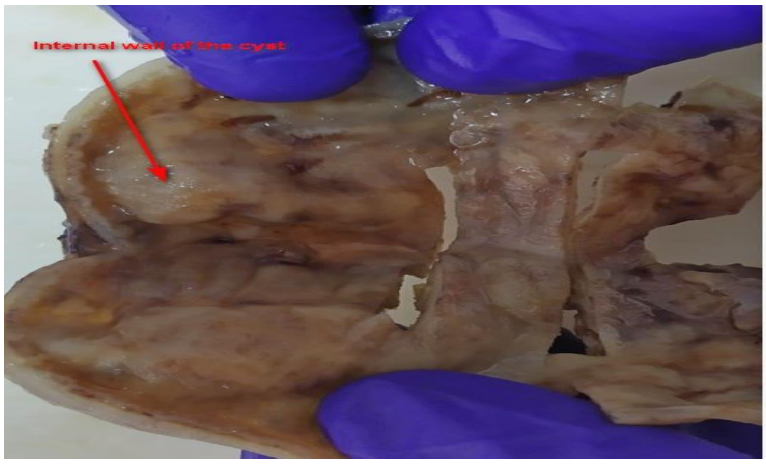

Figure 1: CT-Scan Coronal and Axial planes of the abdominal cavity

A 2815g 5-day-old male patient was born at 37.5 weeks gestation with an APGAR score of 9-10-10. An ultrasound scan identified an intra-abdominal lesion suggesting a megacolon diagnosis. After birth, further investigations revealed a large extrahepatic unilocular fluid-filled structure measuring 80x30 mm, suggesting a mesenteric cyst, cystic lymphangioma, or composite hepatic hamartoma. A cystic mass attached to the terminal ileum was noted at laparotomy, and the cyst and intestine were closely related. The ileon-cyst complex was resected and end-to-end interrupted primary anastomosis using vicryl 4/0 was performed. The gross pathological specimen showed a 75x10 mm intestinal fragment with ileal mucosa of normal appearance joined to a 80x35cm cystic structure containing mucus without luminal communication. The cyst contained mucus covered by glandular epithelial tissue and shared musculature with the intestinal portion, covered by gastric tissue. The cystic structure shared musculature with the intestinal portion, covered by gastric tissue within normal histological limits. The specimen was classified as Type 1B intestinal duplication according to the Long classification. The patient's post-operative period was uneventful, and at six months, he is thriving well without any complications.

Diagnosis of intestinal duplications is made using chest X-rays, ultrasonography (USG), CT computerized axial tomography, contrasted studies, and diagnostic laparoscopic techniques. In the prenatal period, antenatal ultrasound scan and magnetic resonance imaging can be used for diagnosis. Contrast radiological studies can also be used for differential diagnosis of mesenteric cysts, especially the cystic type. Histological examination is the definitive diagnosis.